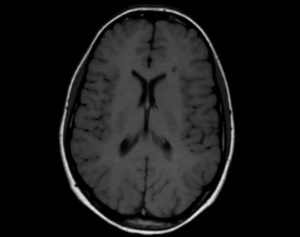

Во время сканирования используют пульсовые последовательности с различными интервалами — «инверсию восстановления» (IR) и «спиновое эхо» (SE). Патологические изменения при МРТ проявляются по-разному, в зависимости от типа пульсовой последовательности:

- очаги демиелинизации при режиме IR выглядят черными;

- очаги демиелинизации при режиме SE выглядят белыми.

Нормальное белое вещество мозга визуализируется:

- на Т1 взвешенных изображениях светлым;

- на Т2 ВИ – темным.

Очаги демиелинизации за счет увеличения содержания воды имеют сигнал:

- пониженной интенсивности на Т1-ВИ;

- повышенной на Т2-взвешенных изображениях.